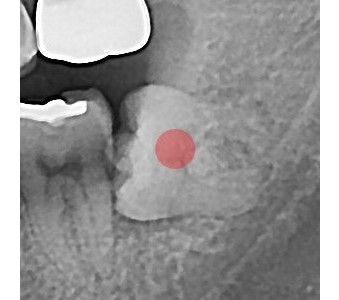

以成果证明实力。

国际摩牙齿科

真实临床案例